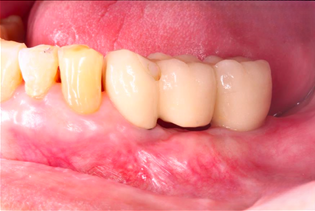

Before Treatment

Fig 5: 6 months review after new implant placement

Three months later, an implant-supported bridge was constructed by our prosthodontist, with ongoing 6-month reviews (Fig 5). Radiographs at the 2-year review confirmed stable bone levels around the implants (Fig 6).